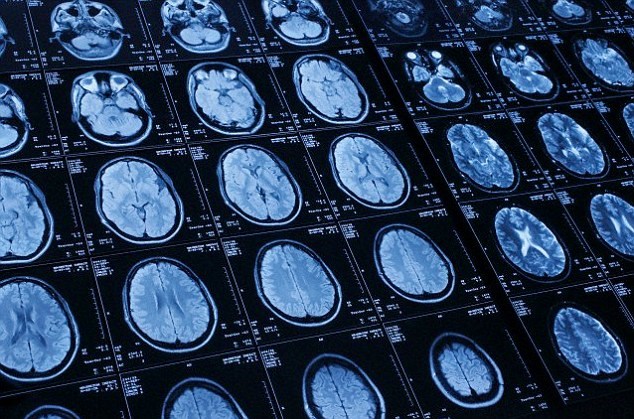

Ngày 7/6, các nhà khoa học Mỹ tuyên bố công nghệ chụp cắt lớp não có thể giúp phát hiện sớm những thay đổi về mặt chức năng ở trẻ có nguy cơ cao bị chứng tự kỷ ngay từ khi trẻ khoảng 6 tháng tuổi, từ đó giúp dự đoán khả năng mắc trước 2 tuổi.

Trong nghiên cứu mới do các nhà khoa học đến từ Đại học Carolina Bắc (UNC) phối hợp cùng các chuyên gia Đại học Dược Washington thực hiện, các tác giả đã sử dụng công nghệ chụp cộng hưởng từ để kiểm tra khả năng kết nối chức năng não bộ của 59 trẻ 6 tháng tuổi khi các bé đang ngủ.

Kết quả tổng hợp và phân tích cho thấy hệ thống giúp dự đoán được 9/11 trẻ thực sự mắc chứng tự kỷ khi các em 2 tuổi. Các nhà nghiên cứu tin tưởng việc phân tích các hình ảnh chụp cắt lớp não bộ có thể giúp dự đoán chính xác chứng tự kỷ ở nhóm trẻ có nguy cơ cao, tuy nhiên cũng cho rằng cần tiến hành thêm các nghiên cứu trên diện rộng để có kết luận chính xác.